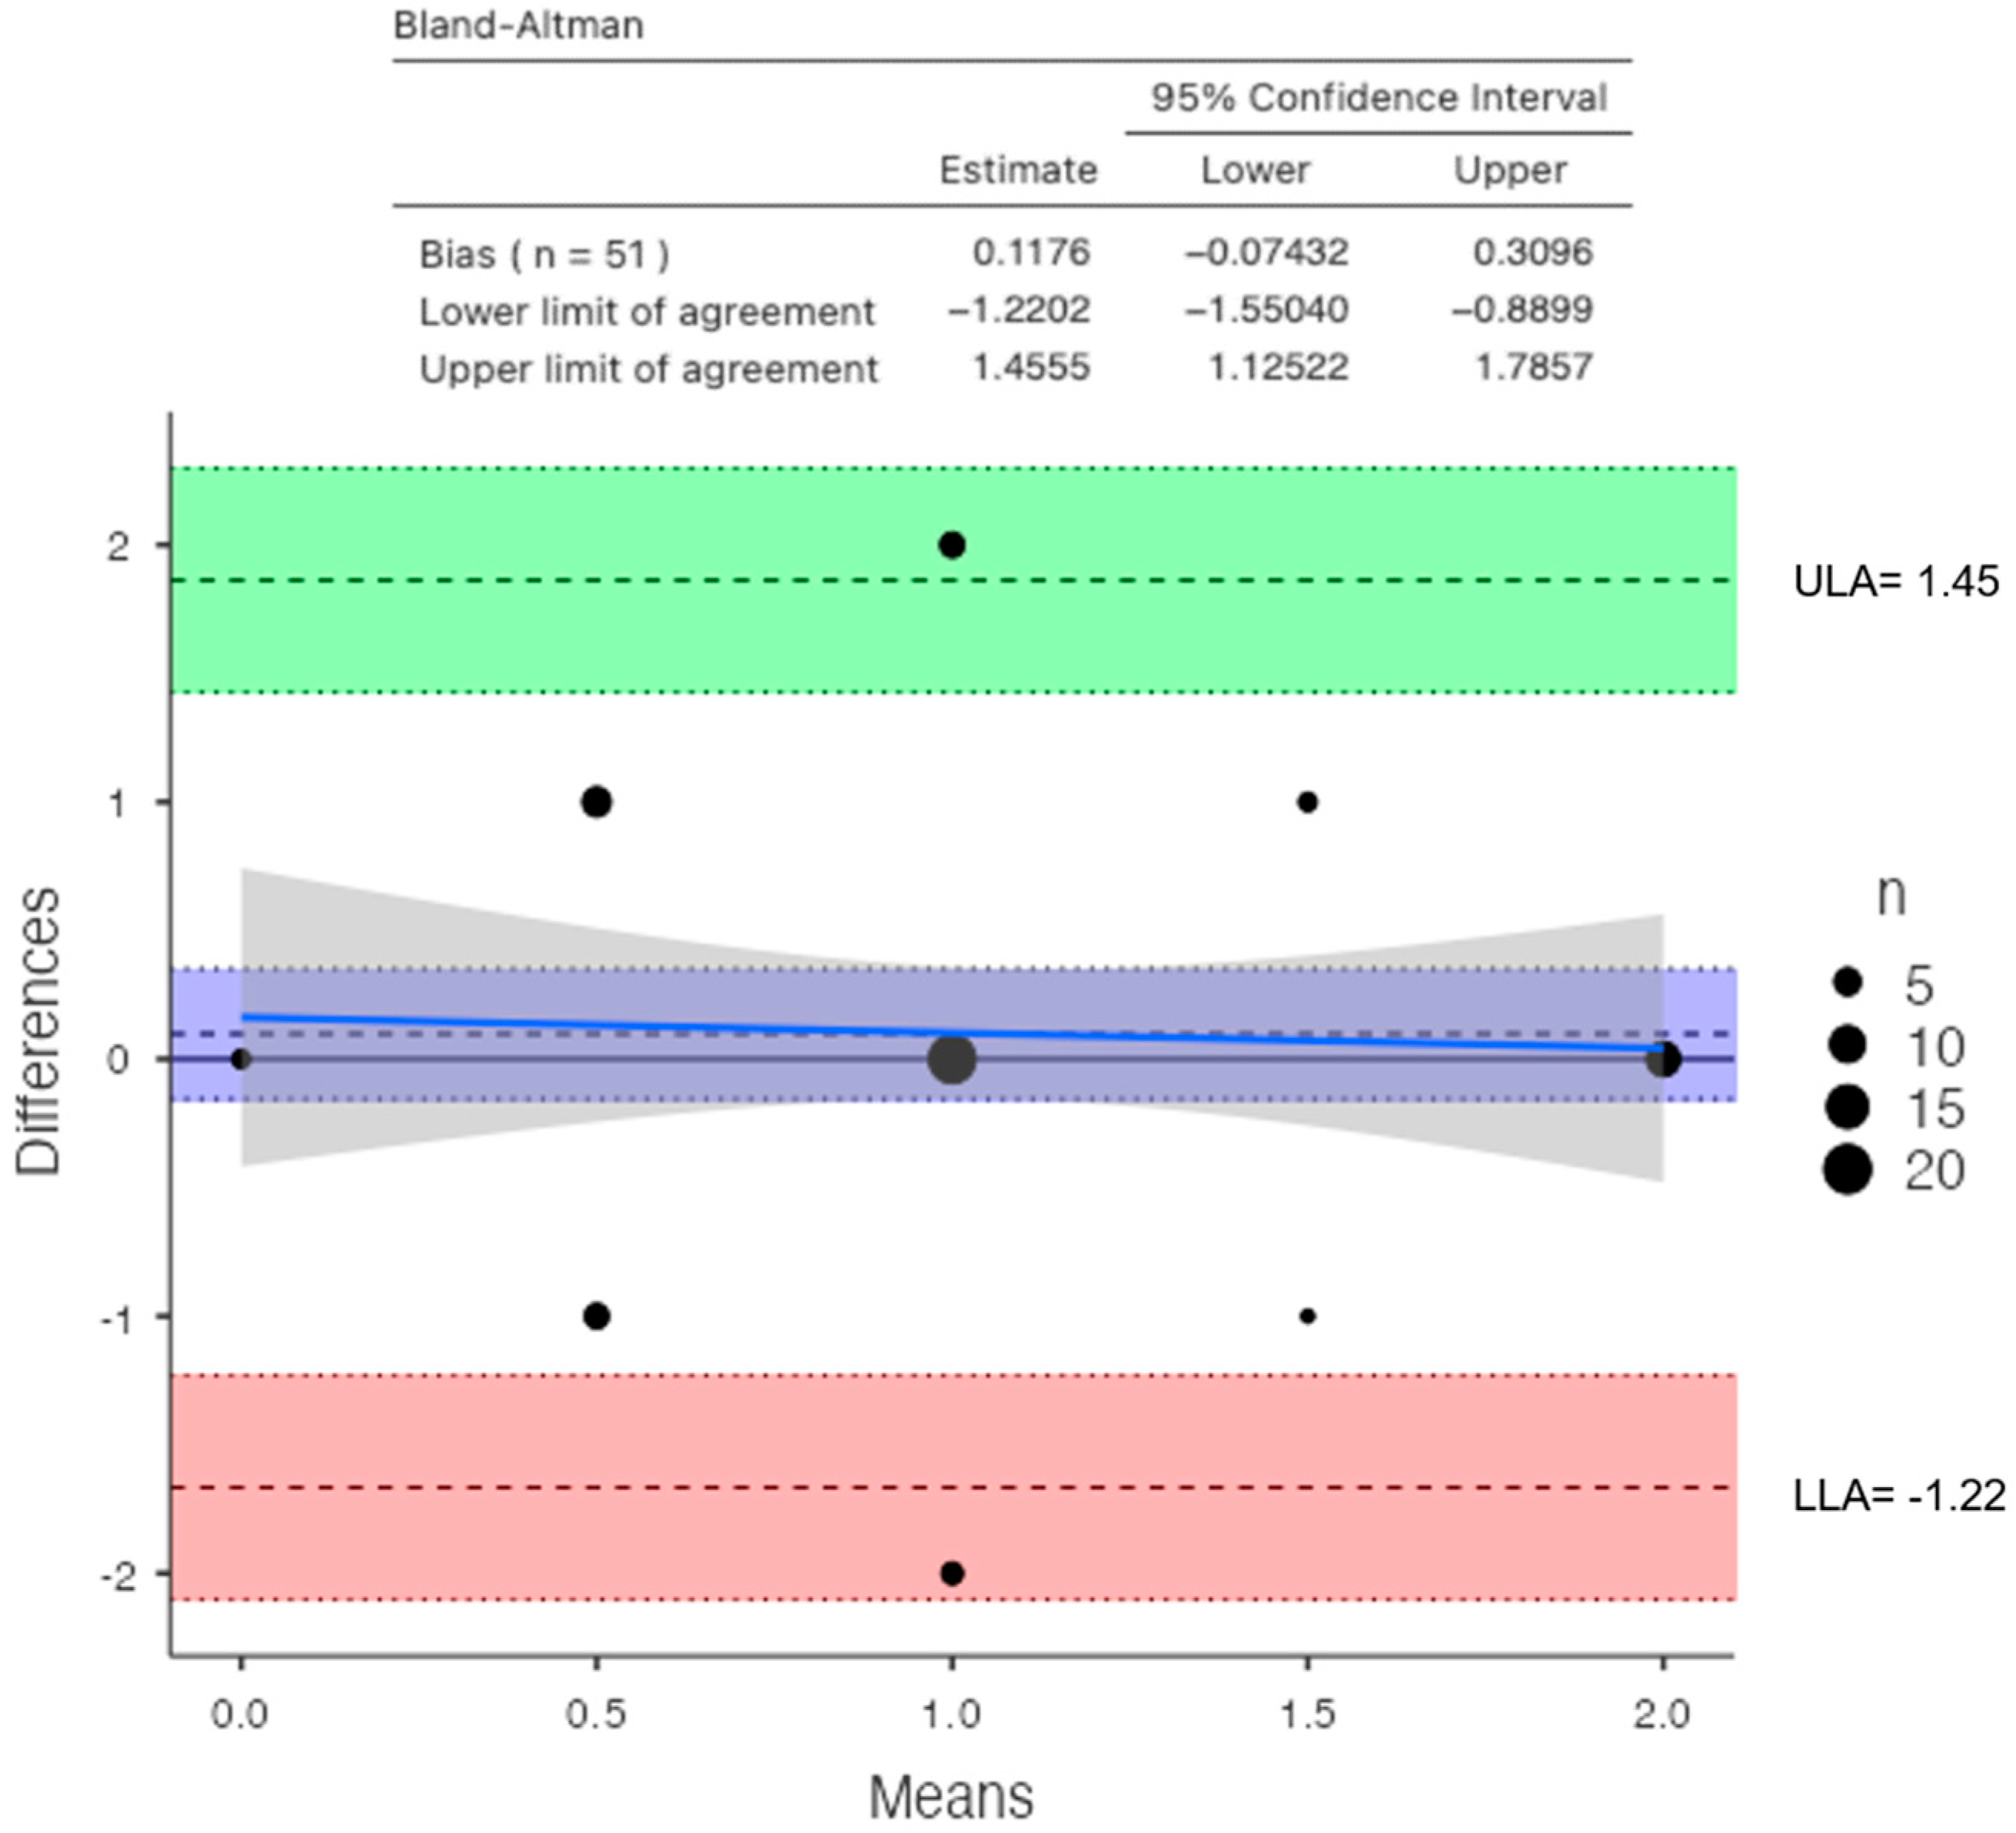

3. Results